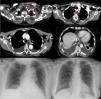

Axial computed tomography slices showing left laterocervical-supraclavicular collection, with diffuse extension throughout all mediastinal compartments (circled) and bilateral pleural effusion. (A) Posteroanterior radiograph of chest after removal of left pleural drainage tube, with the right pleural drainage tube still in place. (B) Posteroanterior radiograph of chest during follow-up, 3 months after the episode, showing complete resolution of bilateral pleural effusion.

We report the case of a 60-year-old patient with a history of arterial hypertension, dyslipidemia, and hypothyroidism receiving medical treatment. After a violent sneeze, she developed left supraclavicular swelling and dizziness, which prompted her to visit the emergency room. The chest radiograph revealed bilateral basal pleural effusion; cervical-chest computed tomography (CT) showed left laterocervical-supraclavicular collection extending to all mediastinal compartments, with bilateral pleural effusion (Fig. 1), interpreted by the radiologist as hematoma following a violent sneeze. A wait-and-see approach was adopted, and after bilateral progression of the effusion was confirmed on X-ray, endopleural drainage tubes were placed in both sides. Fluid with a chylous appearance was obtained from both hemithoraces, and analysis of samples from both sides confirmed sterile exudate with a high triglyceride concentration (2241mg/dl in the right hemithorax and 2160mg/dl in the left). After diagnostic confirmation of bilateral chylothorax, dietary treatment was initiated, with restricted fat intake. Fluid collected from both drainage tubes reduced progressively, becoming serous in appearance after the introduction of dietary restrictions, confirming the biochemical resolution of the chylothorax. In view of the patient's favorable progress, no other therapeutic measures were introduced, and the pleural drainage tubes were removed from the left side after 48h (Fig. 1A) and from the right side after 5 days. After removal of the drainage tubes, radiological monitoring confirmed bilateral resolution of the effusion. Resolution of clinical and radiological signs and symptoms were confirmed in outpatient follow-up (Fig. 1B).